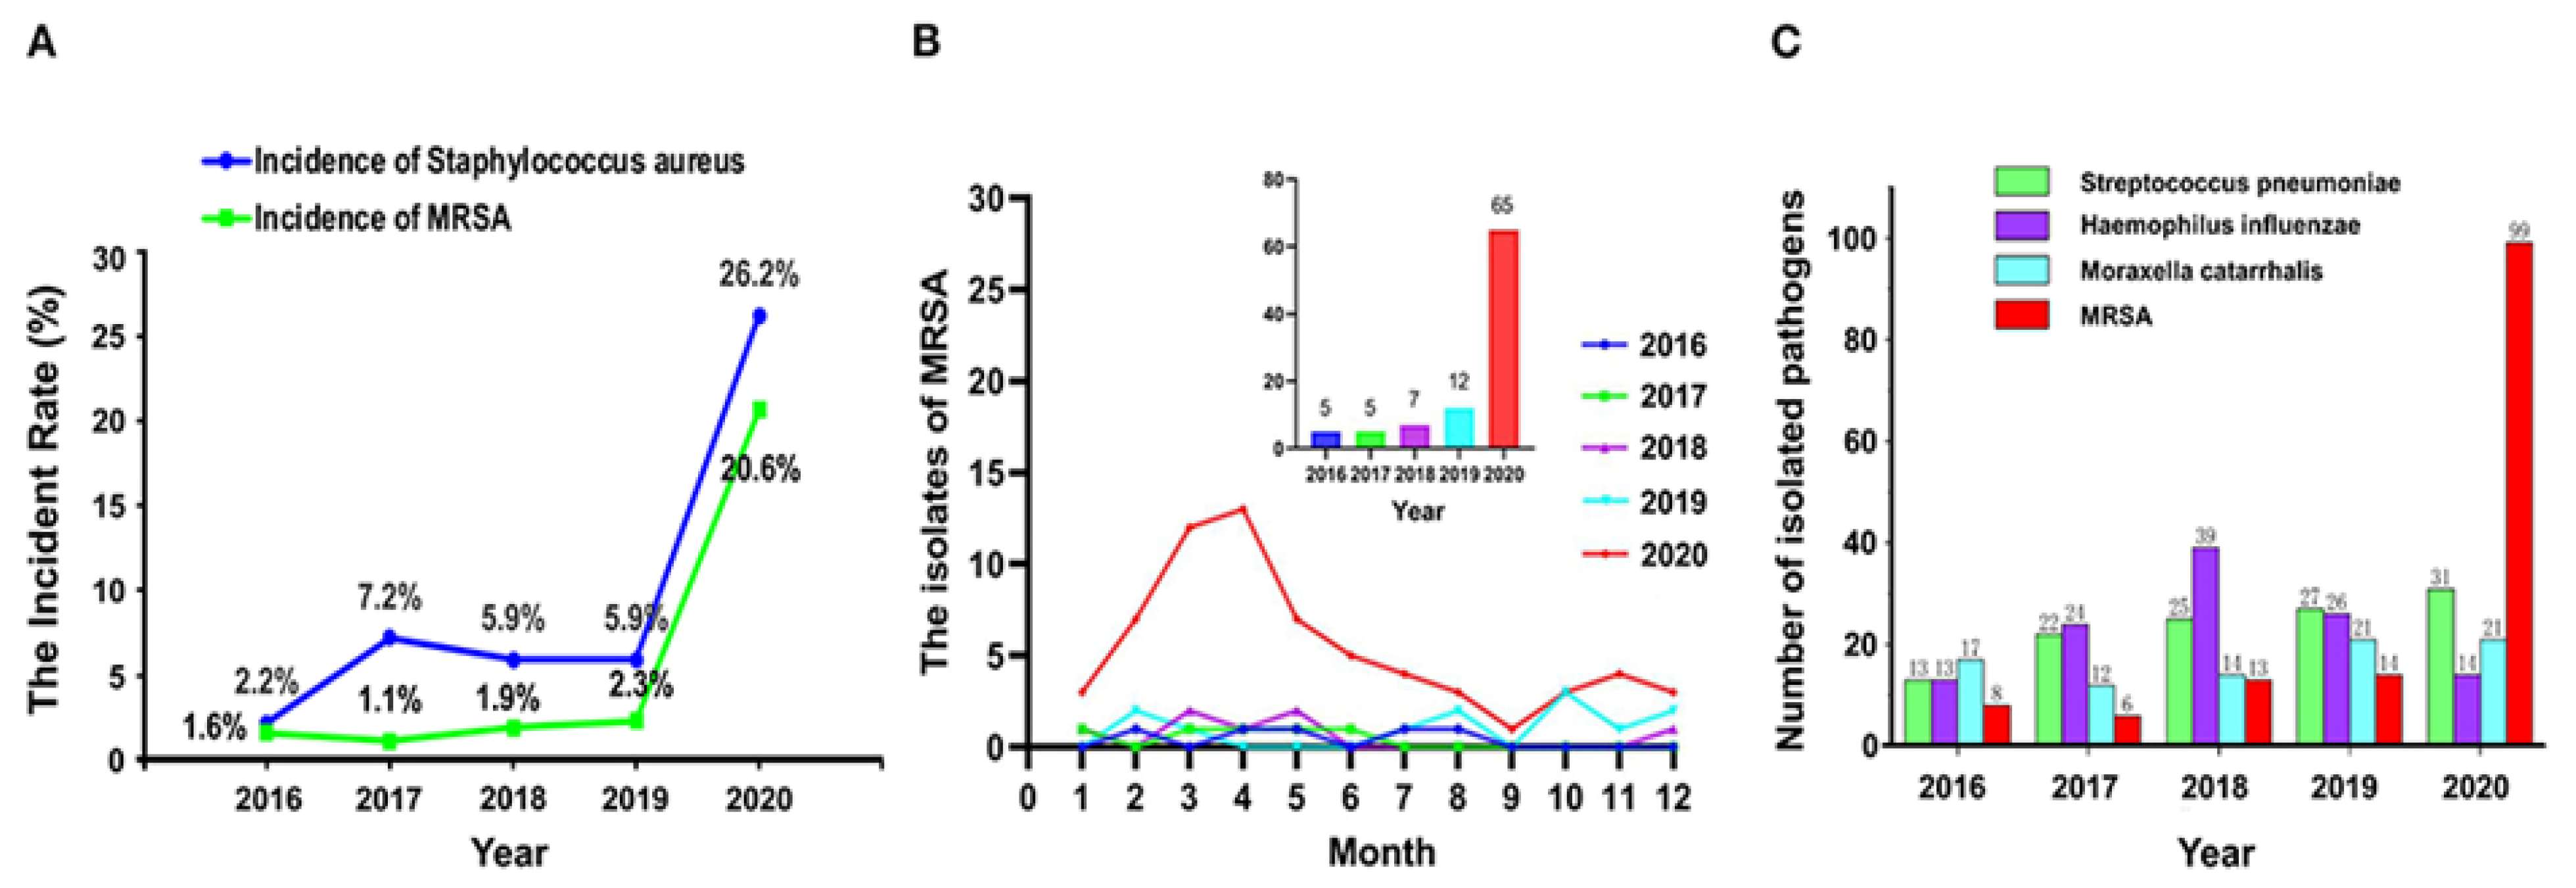

1. Introduction

- Yang, M.; Feng, Y.; Yuan, L.; Zhao, H.; Gao, S.; Li, Z. High Concentration and Frequent Application of Disinfection Increase the Detection of Methicillin-Resistant Staphylococcus aureus Infections in Psychiatric Hospitals During the COVID-19 Pandemic. Front. Med. 2021, 8. [Google Scholar] [CrossRef] [PubMed]